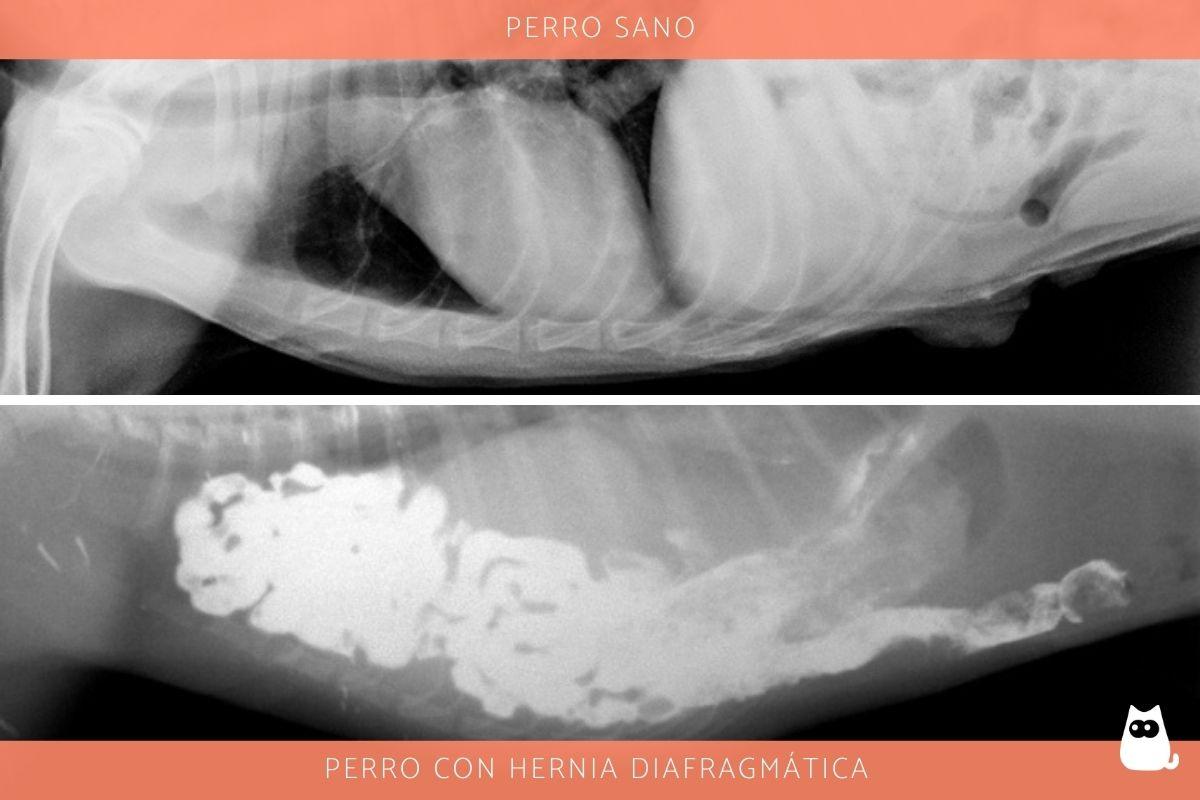

Lo primero que se debe hacer en el diagnóstico de una hernia diafragmática es realizar radiografías, especialmente de tórax para evaluar los daños. En el 97 % de los perros se observa una silueta del diafragma incompleta y en el 61 % se determinan asas intestinales llenas de gas en la cavidad torácica. Puede observarse contenido en el espacio pleural, que puede ser un hidrotórax por efusión pleural en casos recientes o un hemotórax con hemorragia en los casos más crónicos.